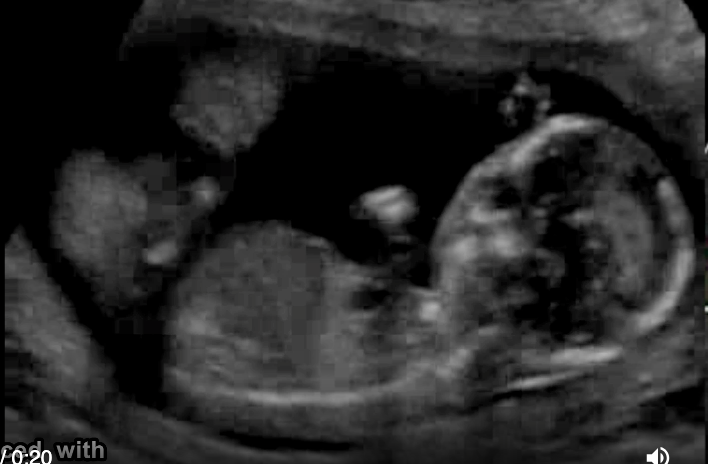

a pt has recent acute onset HTN, nausea, vomit. she has no pain, cramping, or vaginal bleeding. a prior US at 6w indicates the pregnancy should now be 17w6d GA. the image shows strong suspicion of

.

video is of trophoblastic gestation/molar - most fetuses have asymmetrical large head + small body

a) trisomy 21

b) triploidy

c) trisomy 13

d) trisomy 18